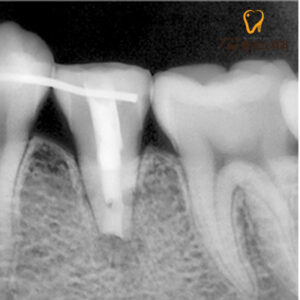

수암동치과 치아재식술의 과정으로는

먼저 치아를 발치한 후 치근 끝을 잘라내고

신경관을 치과 재료인 MTA를 사용하여

충전하게 됩니다.

고정을 위해 옆 치아에

스플린트를 달아 고정해 두었고,

시간이 지남에 따라 치아가 고정되어

잘 아문 모습을 볼 수 있었습니다.